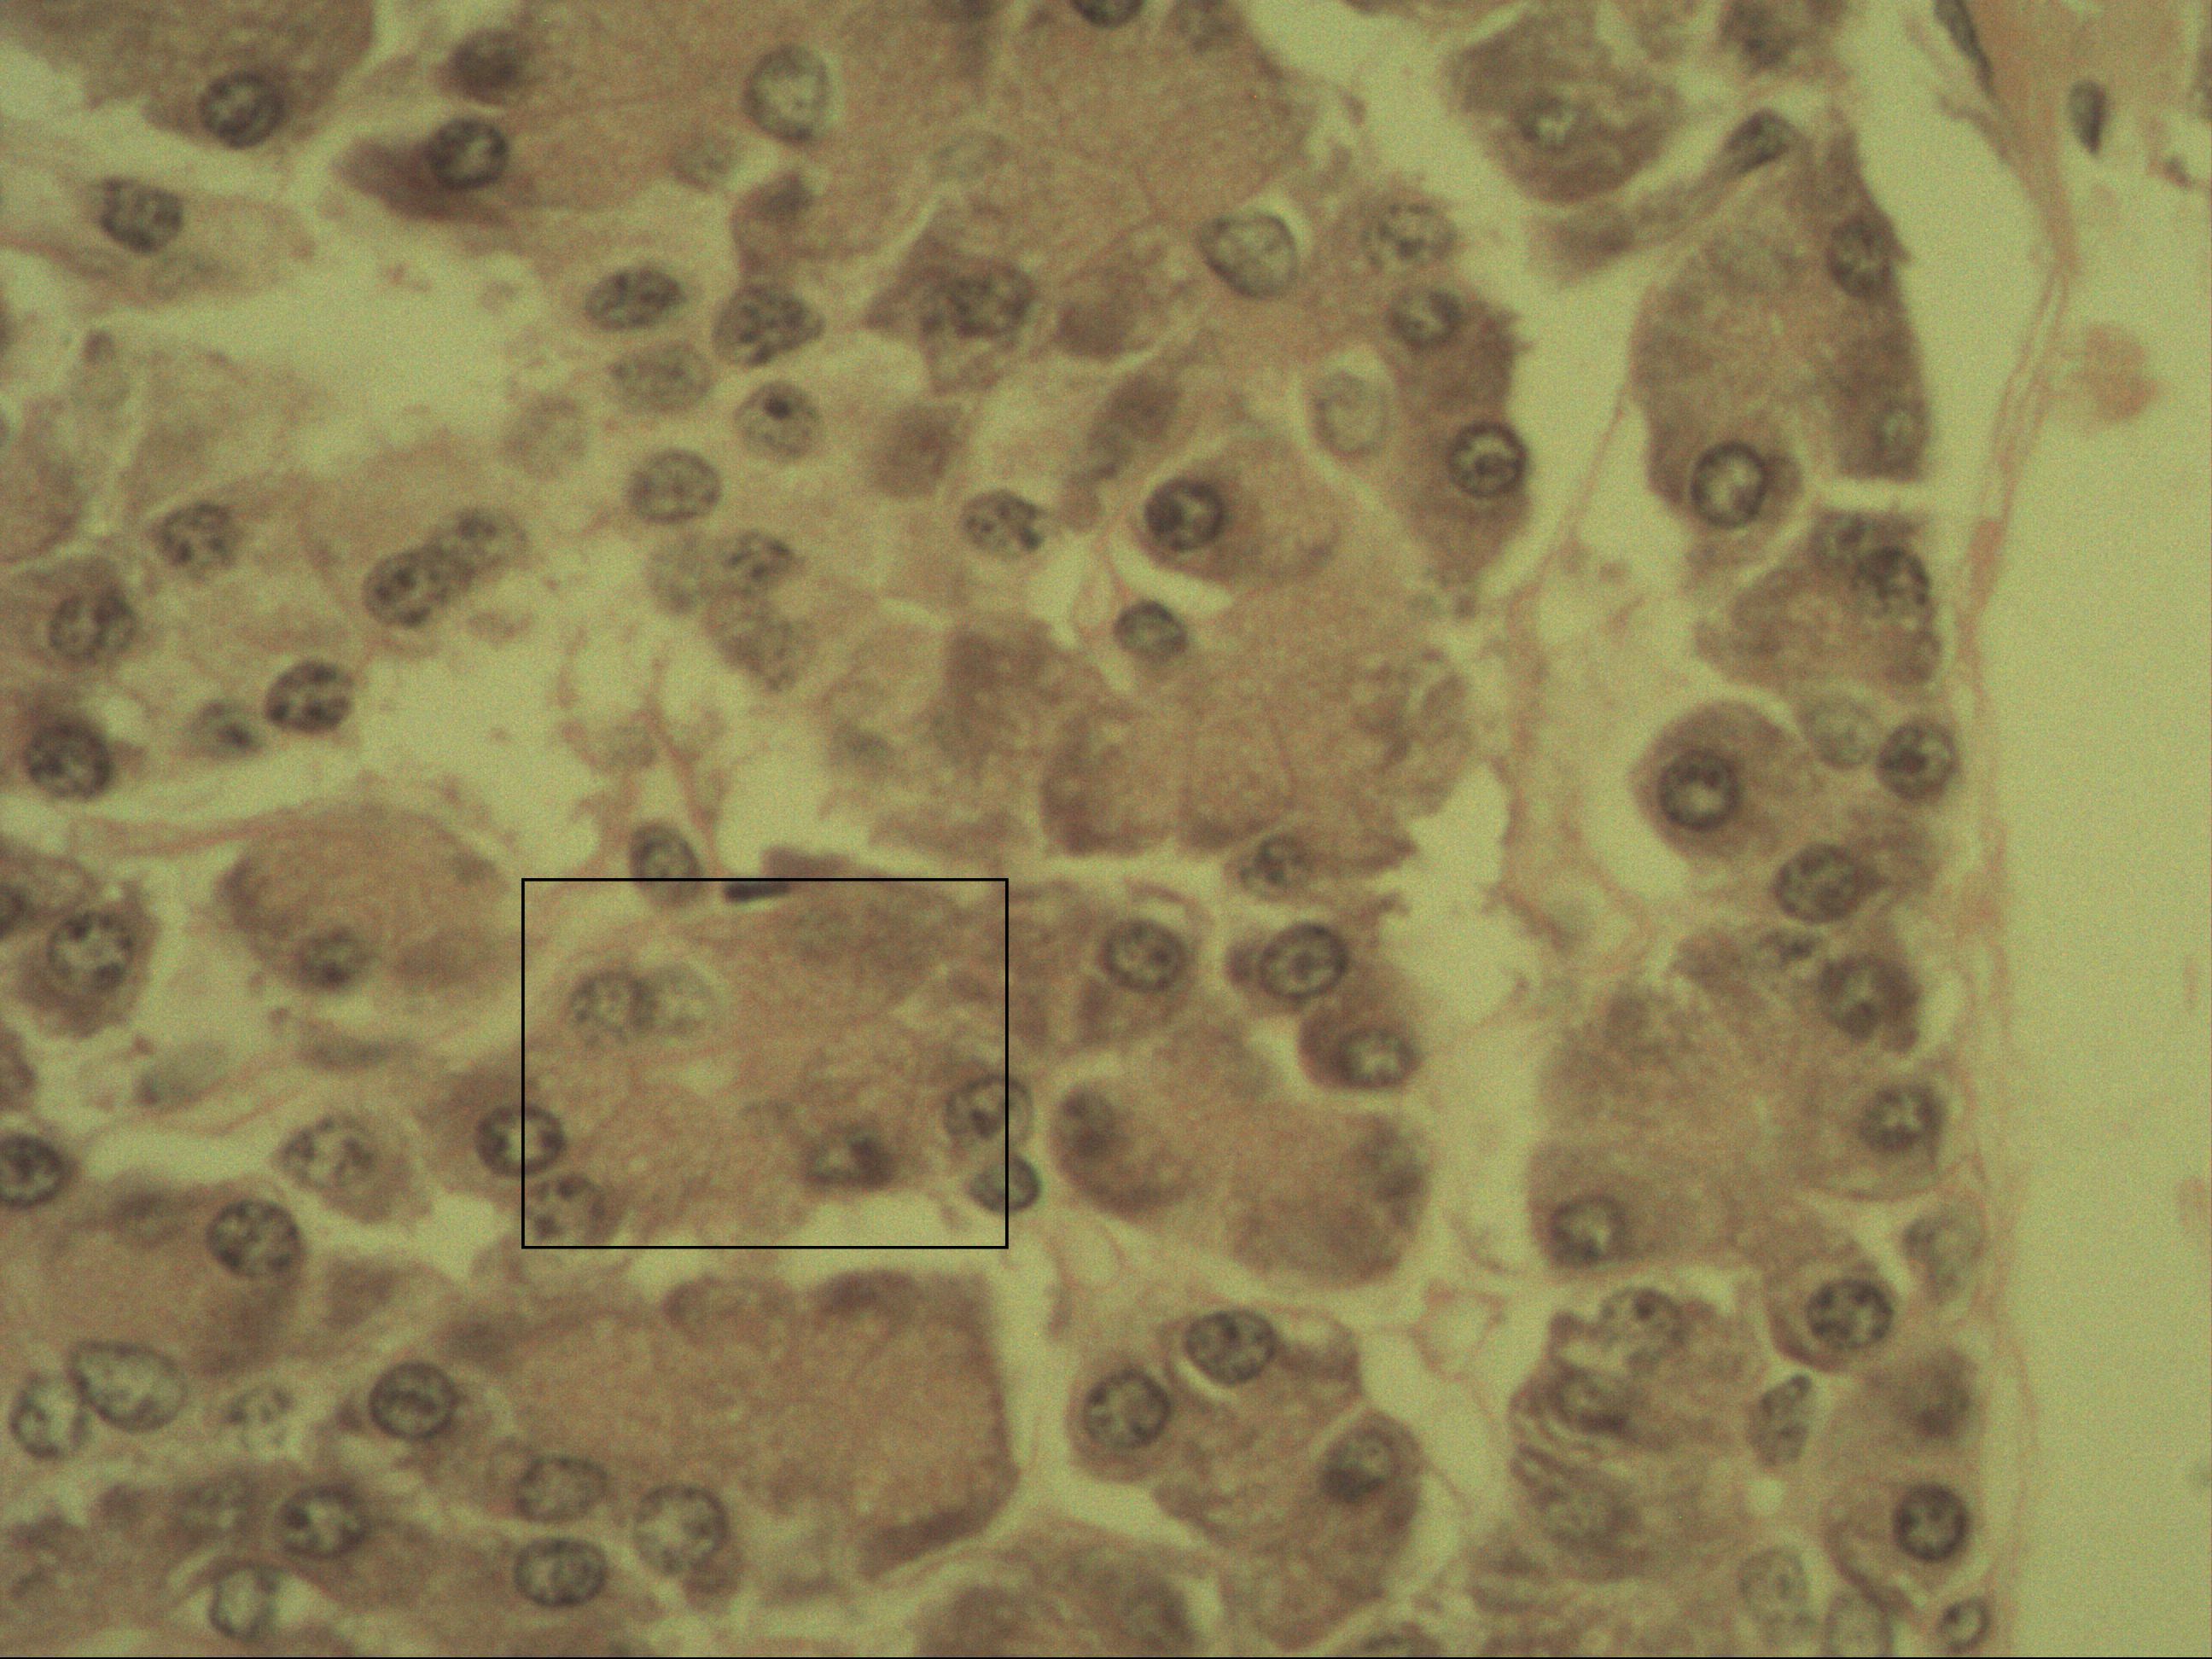

Endokrine Drüse der Langerhans-Insel, Sekretion von Hormonen direkt ins Blut

Zellkern mit überwiegend hellen Euchromatin

Endokrine Drüsen geben ihr Sekret direkt in die Blutgefäße ab. So auch hier bei den Langerhans-Inseln: Die endokrinen Drüsen der Bauchspeicheldrüse schütten vornehmlich Insulin und Glucagon zur antagonistischen Regulierung des Blutzuckerspiegels aus.